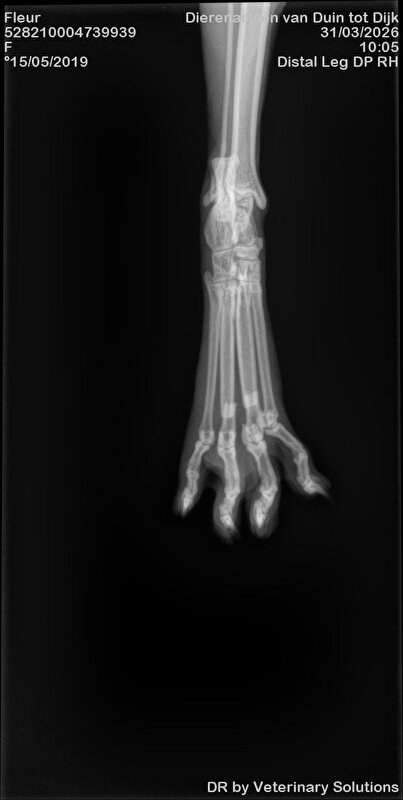

Dag 2: ik laat Fleur achter voor het maken van de foto's. Aan de assistente vertel ik dat Fleur zich goed gedraagt. Fleur is nml best een lief poesje. Er worden 3 foto's gemaakt en deze hoop ik nog te ontvangen om hier te kunnen plaatsen. 2 teentjes gebroken en 1 bot dusdanig naar buiten gekanteld dat deze bijna door steekt.